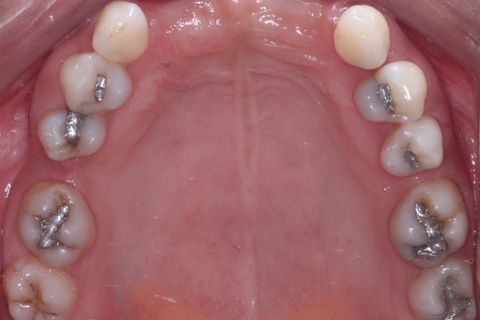

Foto oclusal superior

Foto Oclusal superior sem a Prótese Parcial removível